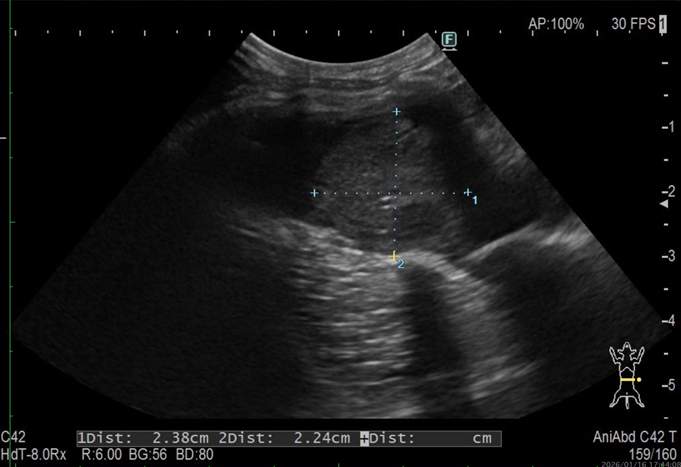

<腹部超音波検査>

異常は認められなかった